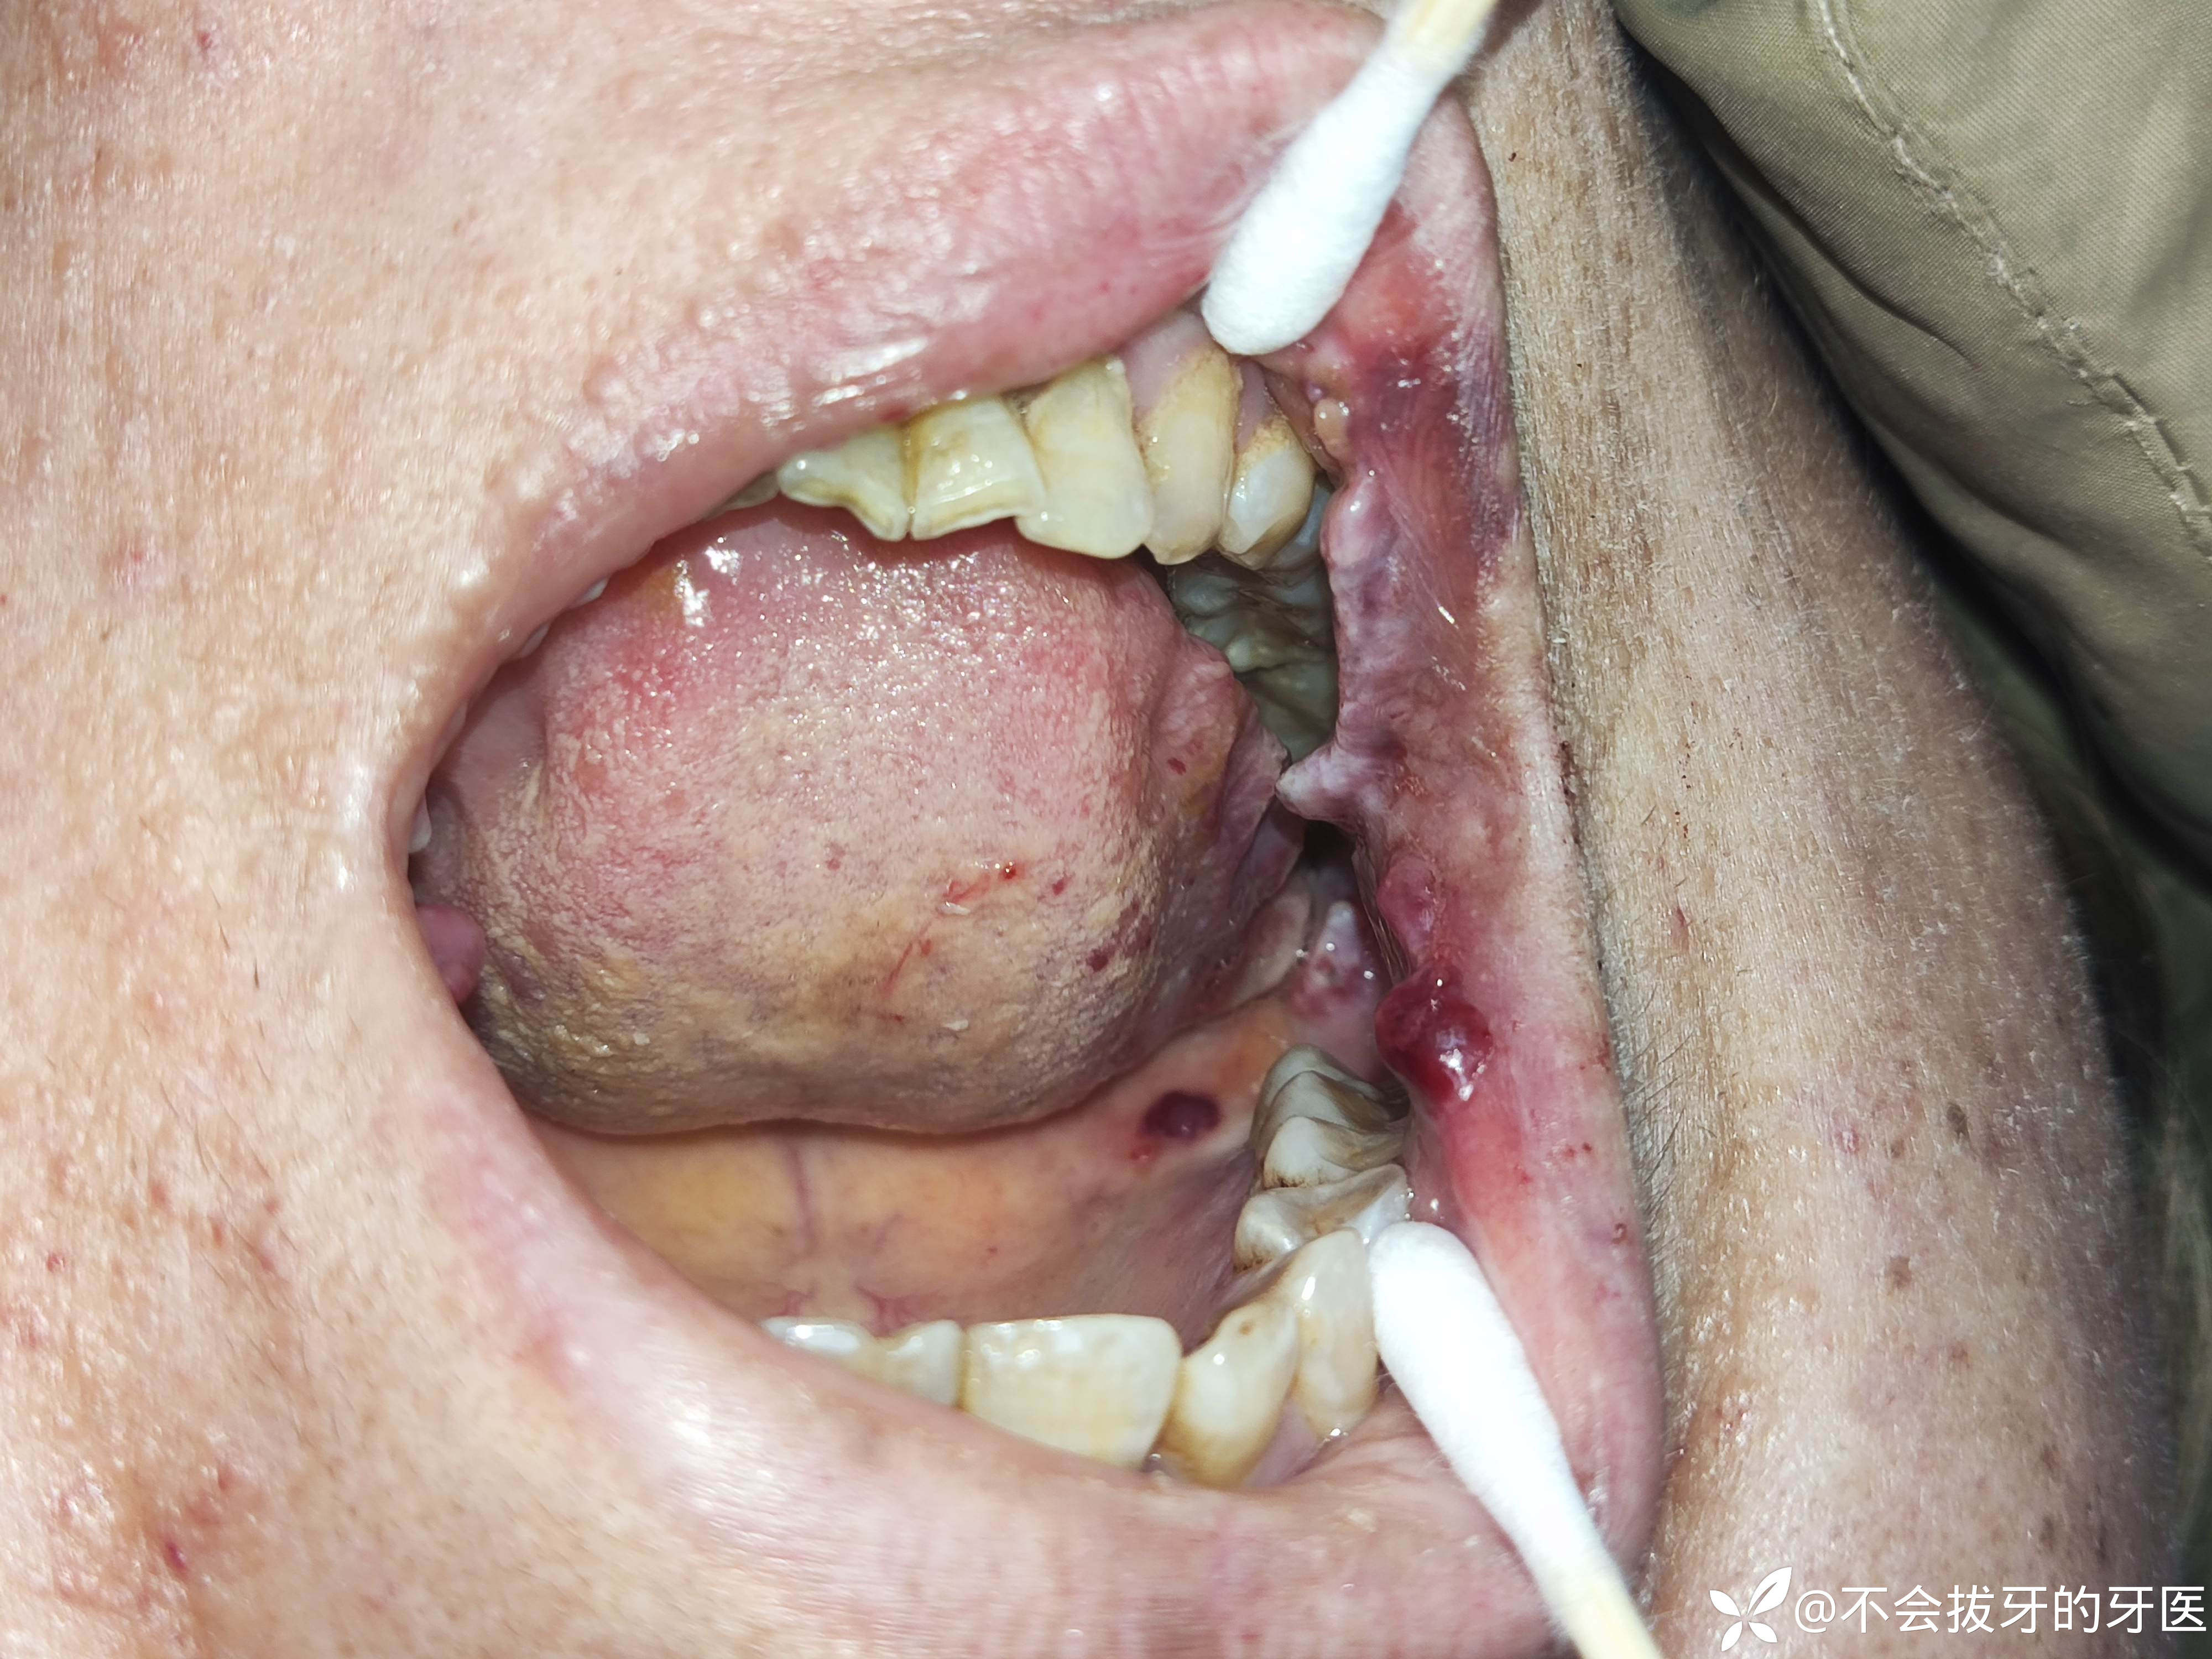

患者因口腔疼痛,无法进食开诊,口腔检查如图所示。患者既往曾检查发现血小板为2,后经过治疗好转。体检曾因肌酐过高诊断肾病。第一次来院时我考虑左侧舌头溃烂、触诊疼痛重,对应位置有残根锋利锐尖,再一个口腔及全身病复杂。建议上级医院就诊。结果上级医院黏膜专科及颌外肿瘤专科可能是小大夫看的吧也没说出个啥所以然,患者再次来我这,想拍个ct,我发现舌部病损好转,我磨除了锋利锐尖,先在咨询大家,下一步诊疗方案怎么整?感谢感谢🙏

患者部分化验结果如图所示。患者目前吃药有尿毒清颗粒、骨化三醇胶丸、骨松宝片、艾曲波帕乙醇胺片。